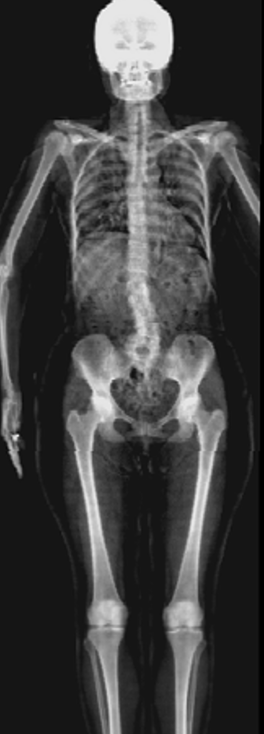

3.4 DXA to MRI Volume Generation

DXA is a single image data modality that is similar to X-ray but includes other non-bony information such as tissue mass [67]. It measures bone mineral density and body fat composition. The radiation level is low enough that it is acceptable for conducting studies of healthy participants, such as the UK Biobank. In order to leverage X-Diffusion to synthesize the MRI volume from a single DXA (as in Figure 3), they have to be aligned, and registered. Note that, the size of the DXA does not match the MRI () and the scans are not registered. The two modalities in UK BioBank were not taken simultaneously but close in time hence why we believe registration is feasible for these two sequences as illustrated extensively in [79].

In order to tackle this domain gap, we leverage a registration network [79] paired with a X-Diffusion to achieve DXA to MRI slice generation. [79] introduced a multi-modal image-matching contrastive framework, that is able to learn correspondences between DXA and middle coronal MRI slices. These networks extrapolate the DXA scan by a transform to the coronal MRI slice by harnessing the embedded patterns and features of the DXA and the coronal MRI mid-slice. X-Diffusion is then trained on the registered DXA () and corresponding MRI slices in () in the target MRI volumes and is able to produce precise MRI volumes that align with the DXA scans (see Figure 5 left). The other details are similar to Section 3.2 and Section 3.3.

Notably, X-Diffusion achieves state-of-the-art dB for a few input slices while baselines require more than 60 input slices to achieve similar performance (Figure 7). The margin is more than 12 dB PSNR for the 1-slice input in both the BRATS and the UK Biobank benchmarks (see Table 1 and Figure 6). For reference, two randomly sampled MRIs from UK Biobank would have a PSNR of 15.95 dB 0.36 (on 4800 randomly sampled examples). Omitting the preprocessing step of alignment DXA to MRI, leads to a drop of PSNR on average by 2.87 dB (29.01 dB 26.14 dB). The slices from 3D reconstructed volumes at varying depths and axis of rotation, visually match the ground truths for both brain and whole-body scans (see Figures 4 and 5 left). We also plot the error map (Figure 3) and the spread of the error (Figure 5 right) of such X-Diffusion generations to highlight the differences with the ground truth MRIs.

Preservation of Spine Curvature. For the spine segmentation on UK Biobank, we use a UNet++ model [83] with Dice Loss. We use a model trained to predict curves on DXA on UK Biobank [11]). We measure the Pearson correlation factor [11] of spine curvature measured on the generated MRIs where the input is a single MRI coronal slice, a single sagittal slice, or from the paired DXA, against the curvature of reference real MRIs of the same samples. The correlation coefficients are 0.89 for the coronal MRIs, 0.88 for the sagittal MRIs, and 0.87 for the DXAs on the test set of 308 human-annotated angles. We can then bin the curvature of the spines under different scoliosis categories based on human-annotated angles: mild: , moderate: , and severe . We show the results in Figure 8. This illustrates that the generated MRIs preserve the spine curvature from normal to severe scoliosis cases. Additional details about spine curvature are provided in supplementary material.